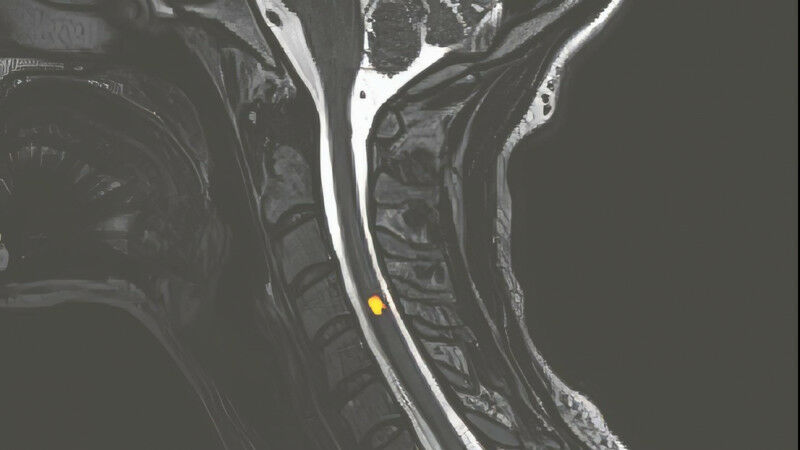

In the area of magnetic resonance imaging (MRI), Prof. Dimitri Van De Ville, the head of EPFL’s Medical Image Processing Lab, has identified two opposing trends.

"The first trend is an increase in the strength of machines’ magnetic fields, enabling them to reveal tiny irregularities such as microscopic injuries and very early-stage cancer cells," say Van de Ville.

Most MRI machines in hospitals today have a magnetic field of 1.5 or 3 teslas s. Engineers at the Alternative Energies & Atomic Energy Commission near Paris have invented a machine with a magnetic field of 11.7 teslas - the most powerful in the world. According to Prof. Jean-Philippe Thiran, the head of EPFL’s Signal Processing Laboratory, "the stronger the magnetic field, the better we can pick up weak signals that are otherwise hard to catch, giving us more granular information."

At EPFL, engineers have developed a 7-tesla machine - powerful enough to map human brains by neural layer in vivo. Prof. Friedhelm Hummel, the holder of the Defitech Chair of Clinical Neuroengineering, explains: "This will give us a better understanding of human brain structures, because for now the exact role of each structure isn’t really clear."